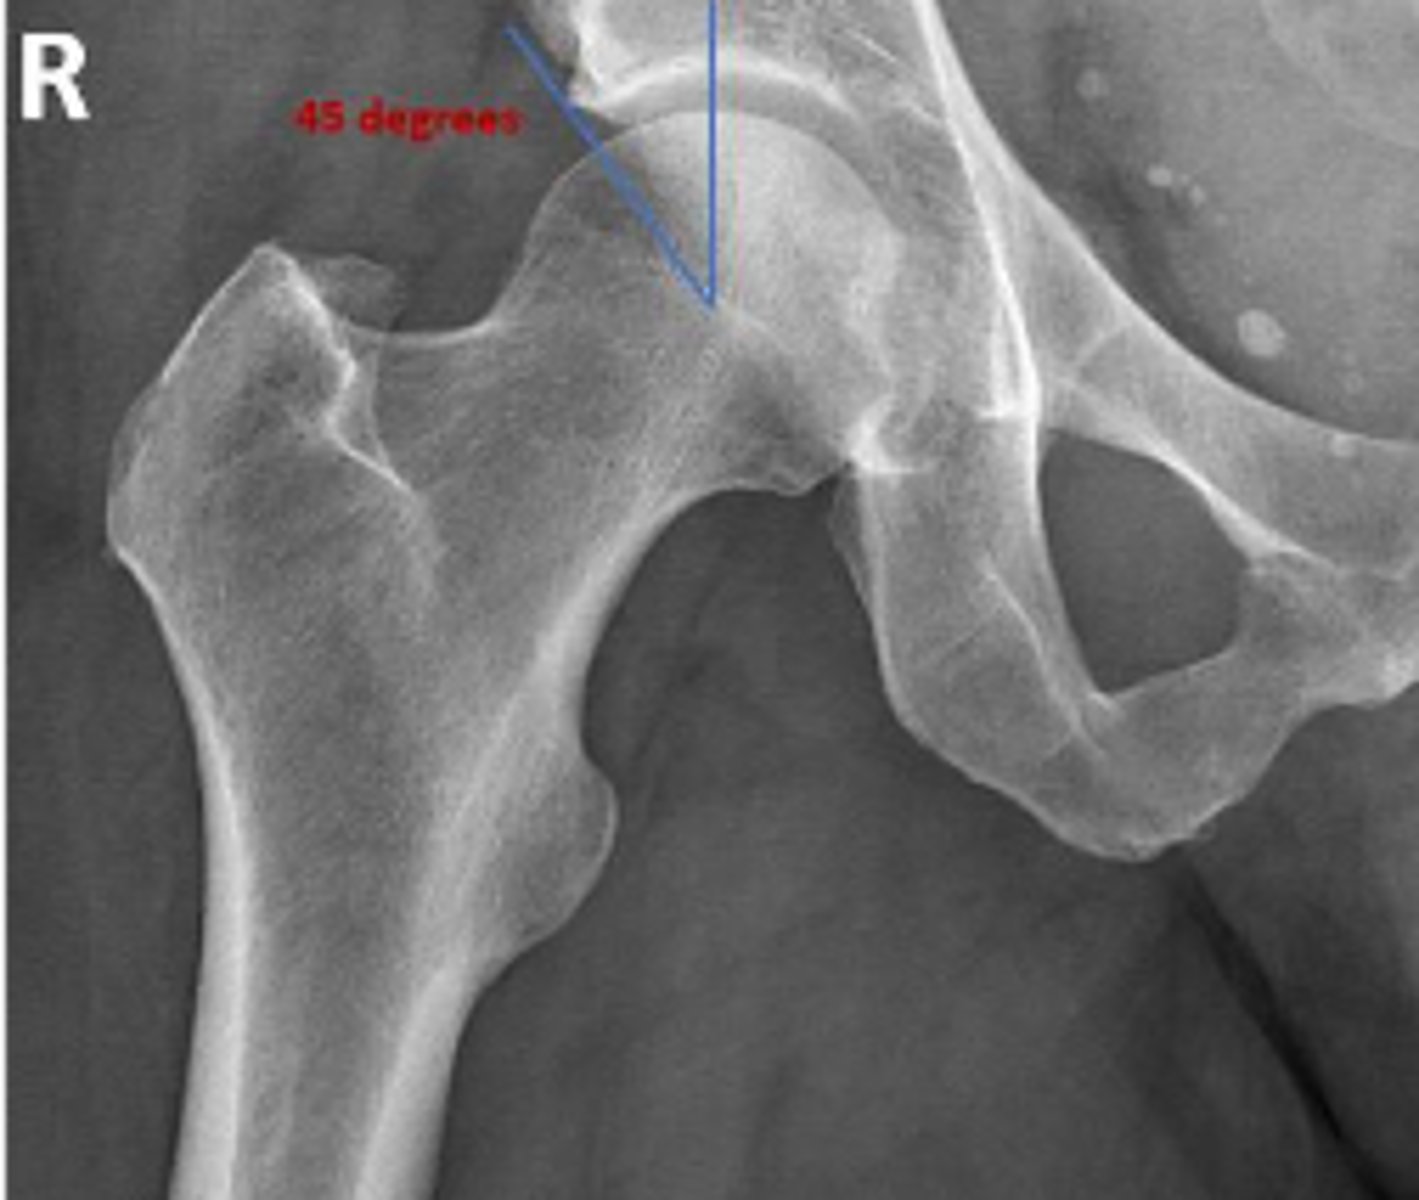

Center edge angle

What is the name of the assessment?

20-40 degrees

What is the normal range for this assessment?

A vertical line is drawn upwards from the center

of the head of the femur.

The second line is drawn from the center of the femur head to the outer superior-lateral aspect of the acetabulum

What are the osseous landmarks for this assessment

No (normal measurement is 20-40 degrees)

Is the measurement within normal limits?

Acetabular dysplasia

Developmental dysplasia of the hip

Name 1 condition that may result in a measurement <20 degrees?

AP pelvis and AP hip views

Name 2 radiographic views for this assessment?